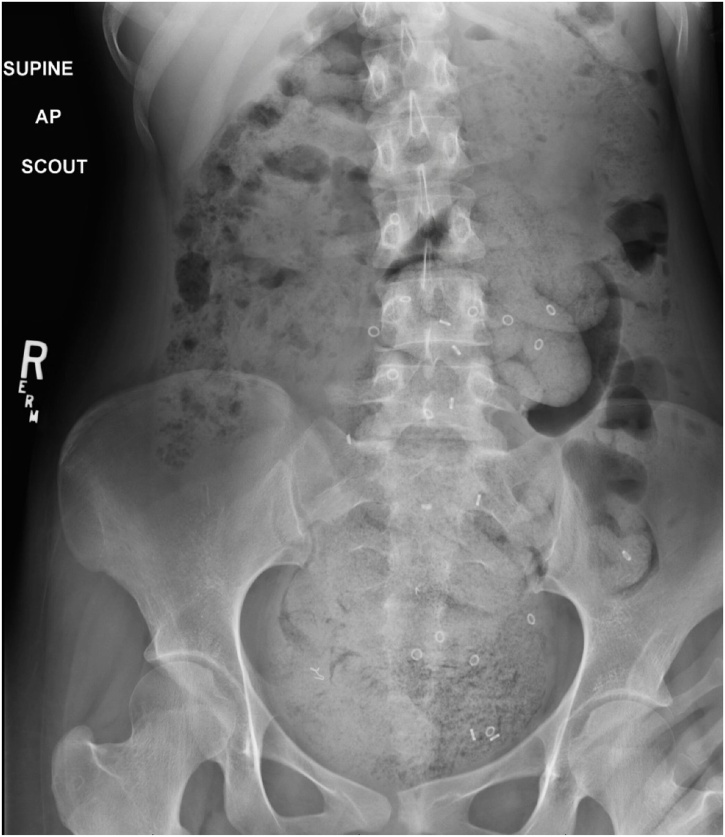

A 19-year-old Caucasian female patient was referred to General Surgery Department after her PCP found megacolon and megarectum in a computed tomography (CT) scan of the abdomen and pelvis (Fig. 1, Fig. 2, Fig. 3). Her evaluation and diagnostic procedures were performed by a board-certified general surgeon with colorectal surgery training. She had a lifelong history of intermittent abdominal pain as well as constipation requiring daily laxatives and enemas. Other than that, she did not have a history of medical or surgical problems. She did not smoke and her family history was unknown since she was raised by her aunt. Her abdominal exam was within normal limits. Her ano-rectal exam was normal on inspection, the digital rectal exam demonstrated a normal resting tone as well as hard stool in the rectal vault. The CT scan was significant for a severely distended sigmoid colon and rectum. Her lab work included a complete blood count and a comprehensive metabolic panel, these were within normal limits. Given her presentation the work up included: colonic transit study (Fig. 4), barium enema (Fig. 5) and a full thickness rectal biopsy after rectal de-impaction. Anal manometry was not performed. The colonic transit study (Sitz Marker Test) displayed most of the markers in her sigmoid colon and rectum at day number five. The Barium enema showed similar findings to those of the CT scan which included a dilated rectum starting immediately above the anorectal ring. She was taken to the operating room for a rectal biopsy. Under general anaesthesia and in lithotomy position a manual de-impaction was performed followed by rectal irrigation and a full thickness rectal biopsy. An anoscope was used to identify the level of the target area. In order to include the submucosa 2 full thickness rectal biopsies at 1.5 and 3 cm from dentate line in the posterior aspect were taken. Distal and proximal to this location a 2-0 Vicryl full thickness traction stitch was placed. This allowed total control of the tissue to ensure full thickness specimens. Both defects were closed with running 2-0 Vicryl. The patient tolerated the procedure well; she was discharged home the same day on a soft diet and had no post-operative complications. Pathology results showed the lack of ganglion cells in the submucosa (Fig. 6a-b). Routine H&E staining, as well as Immunohistochemistry stains for S100, Smooth Muscle Actin (SMA) and Calretinin were performed. Both SMA and Calretinin were negative despite appropriate controls which confirmed diagnosis of Hirschsprung’s disease (Fig. 7a-b). The patient was then referred to a tertiary care center. The chief of Pediatric Surgery took over her case. She underwent manual fecal de-impaction, a confirmatory rectal biopsy, laparoscopic seromuscular sigmoid biopsies for levelling and a diverting loop ileostomy for decompression of the dilated colon and rectum. The distal sigmoid colon biopsy showed few ganglion cells; the proximal colon had a normal amount. Seven months later she underwent an uneventful laparoscopic proctectomy with perianal colo-anal pull through procedure of which she recovered well. The operation was uneventful. Two months later her loop ileostomy was closed. She has been doing well. She is having two bowel movements a day with very good control and no longer suffers from constipation.

Fig. 4.

Colonic transit study with most of the markers in the sigmoid colon and rectum.